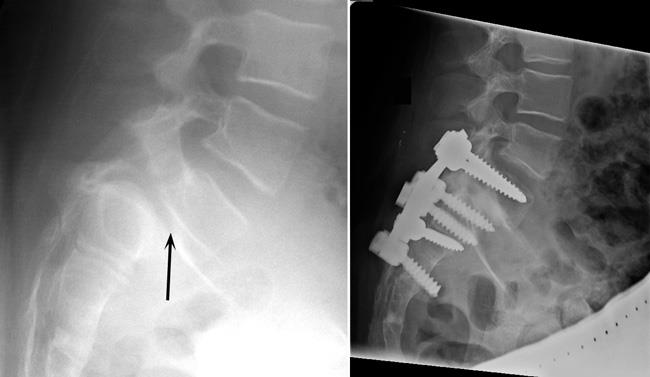

Treatment for spondylolisthesis is similar to treatments for other causes of mechanical and compressive back pain. Surgery is necessary only if conservative treatments fail to keep a patient’s pain at a tolerable level. Surgical treatment for spondylolisthesis must address the presence of mechanical and compressive symptoms. Nerve pressure may require surgical decompression, called decompressive laminectomy of the lumbar spine. Patients needing surgery for spinal instability due to spondylolisthesis will typically require lumbar fusion.